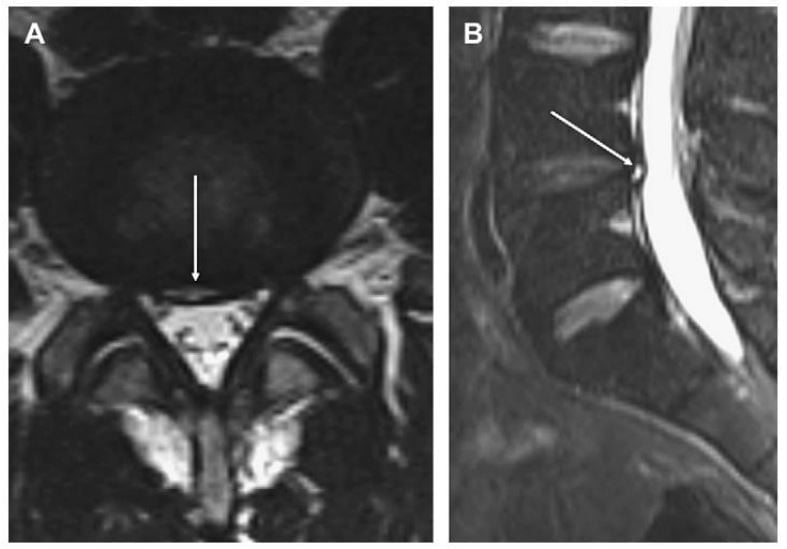

Rách vòng xơ là sự tách đồng tâm, tỏa vòng hoặc ngang của vòng xơ. Rách vòng xơ (Hình 2) có thể gặp ở một số ít ngưới trên 40 tuổi và được xem như là bệnh lý và là yếu tố dự báo thoát vị đĩa đệm. Hầu hết rách vòng xơ không nhìn thấy trên MRI, nhưng rách nhìn thầy được là vùng tín hiệu cao thường có hình liềm và thường gặp ở phần sau đĩa đệm L4-L5 và L5-S1. Rách tỏa vòng là sự phá vỡ vuông góc với trục các sợi collagen. Sự phá vỡ này lan từ nhân collagen đến vòng xơ ở phía ngoại vi đĩa đệm và có thể gây đau nếu rách nằm ngay cạnh hạch rễ thần kinh phía lưng. Hạch rễ thần kinh lưng cho ra dây thần kinh xoang cột sống, dẫn truyền thần kinh phần sau bên của đĩa đệm. Rách đồng tâm là sự phá vỡ song song với trục các sợi collagen. Điều này hình thành nên vùng tín hiệu cao giữa các sợi collagen. Ý nghĩa của rách vòng xơ còn tranh luận và có khi có thể không liên quan với nhu cầu điều trị hoặc với các triệu chứng lâm sàng.

Hình 2. Axial (A) và sagittal (B) T2W thấy một vùng hình liềm (mũi tên) tăng tín hiệu (vùng tăng tín hiệu) ở phần sau củ đĩa đệm L4-L5. Đây là hình ảnh đặc trưng của rách vòng xơ.